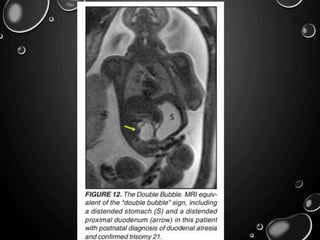

DUODENAL ATRESIA

• DUE TO LACK OF RECANALIZATION OF THE DUODENAL LUMEN FROM

WEEKS 8 TO 10 OF GESTATION.

• ASSOCIATED WITH OTHER CONGENITAL ANOMALIES, INCLUDING TRISOMY

21 (30% TO 40%), ANORECTAL MALFORMATION, ESOPHAGEAL ATRESIA,

AND CONGENITAL HEART DISEASE.

• THE PRENATAL SONOGRAPHIC FINDINGS OF DUODENAL ATRESIA ARE THE

CLASSIC “DOUBLE BUBBLES,” WHICH MIRROR THE MR FINDINGS,

• THE “BUBBLES” REPRESENT THE DISTENDED STOMACH AND PROXIMAL

DUODENUM.

• POLYHYDRAMNIOS MAY BE PRESENT, AS THE SWALLOWED FLUID CANNOT

ENTER THE PROXIMAL SMALL BOWEL LOOPS.